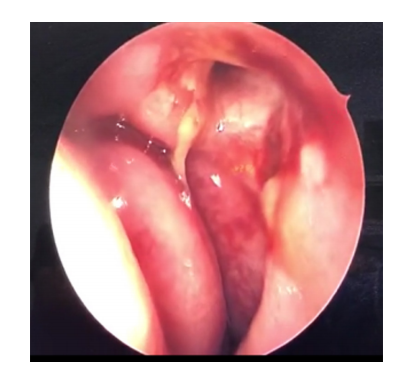

20230203160854_0083.png

图2 医用自交联透明质酸钠凝胶

Figure 2 Medical self-crosslinking sodium hyaluronate gel